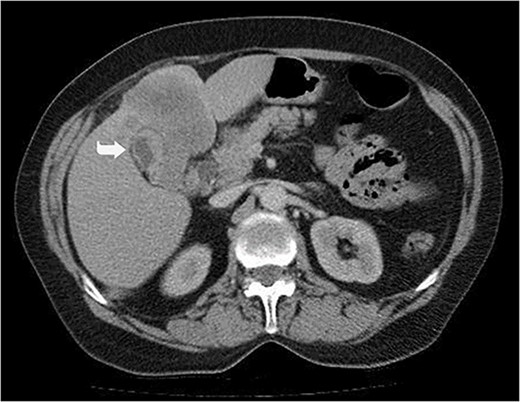

A 59-year-old woman presented with complaints of abdominal pain and abdominal distension for about a month. There was no known systemic disease and no history of previous abdominal surgery. It was learned that the patient had been admitted to the emergency department in another center one month ago with the current complaints and was discharged after medical treatment. Physical examination at the time of admission revealed abdominal distension and diffuse minimal tenderness with no signs of peritoneal irritation. Laboratory tests revealed that hemogram and biochemical parameters were within normal limits, but one of the tumor markers, the patient’s CA 19-9 level was significantly elevated at 855 U/ml (normal range: 0–37 U/ml). Contrast-enhanced CT scan showed a 10×10 cm heterogeneous mass in liver segments 4B-5, extending to segment 6, and free fluid adjacent to the liver and irregular liver contours. Borders of the gallbladder could not be seen. Soft tissues forming nodular mass formation were detected on the omental surfaces (Fig. 1). Computed tomography examination performed at the center where the patient was admitted as an emergency one month ago revealed hypodense lesions measuring 10×8 cm in size in the left lobe of the liver, protruding into the inferior perihepatic area, and 3.5 cm in diameter in segment 5 of the right lobe with no significant contrast enhancement after intravenous injection of contrast material. Perihepatic ascites was not detected and gallbladder size, wall thickness and lumen were normal (Fig. 2). In the light of the radiologic findings, a pre-diagnosis of progressive gallbladder malignancy was considered. The patient was hospitalized in the General Surgery ward for further investigation and treatment. Because of the presence of ascites causing abdominal distension, a percutaneous ascites drainage catheter was placed and 5000 cc ascites drainage was performed. Cytologic examination of the ascitic fluid revealed cell groups with unclear three-dimensional cytonuclear detail among lymphocytes and mesothelial cells with reactive atypia and malignancy was considered suspicious. With the current radiologic and cytologic findings, inoperable metastatic gallbladder carcinoma was considered. Medical treatment was decided by the multidisciplinary oncology council and 18G needle tru-cut biopsy was performed from the 10×10 cm mass adjacent to the gallbladder for definitive tissue diagnosis and adjuvant treatment planning. Histopathologic examination revealed a diagnosis of neuroendocrine carcinoma (NEC) (Fig. 3). Immunohistochemical examination revealed strong staining of tumor cells with CD56 (Fig. 4), synaptophysin (Fig. 5), chromogranin A (Fig. 6), and Ki67 index was >90% (Fig. 7). Weak staining was observed with CK19, CK7, and CDx2, but no staining was observed with CEA and CK20. Morphologic findings were compatible with small cell type. Etoposide and cisplatin chemotherapy was planned but the patient’s general condition deteriorated progressively. The patient couldn’t start chemotherapy and unfortunately resulted in mortality on the 20th day of hospitalization.

Irregular liver contours and perihepatic free fluid (*). Dense heterogeneous mass at the level of liver segment 4B-5, ~10×10 cm in area and extending to segment 6 (Arrow). Borders of the gallbladder could not be seen.